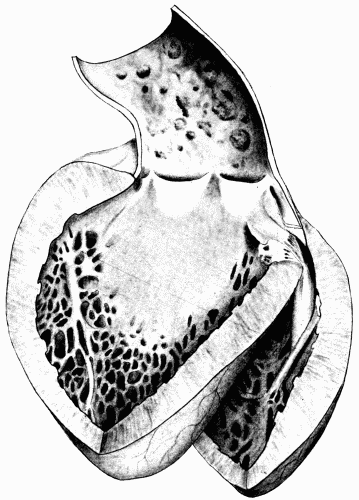

Fig. 11.—Enormous hypertrophy of left ventricle probably due to prolonged increased

peripheral resistance. Note that the whole anterior surface of the heart is occupied

by the left ventricle. The right ventricle does not appear to be much affected.

× ⅔. Fig. 11.—Enormous hypertrophy of left ventricle probably due to prolonged increased peripheral resistance. Note that the whole anterior surface of the heart is occupied by the left ventricle. The right ventricle does not appear to be much affected. × ⅔.

In diffuse arteriosclerosis accompanied by chronic nephritis the heart is always hypertrophied. This is a result, not[58] a cause of the condition. In the pure type, there is hypertrophy only of the left ventricle without dilatation of the chamber. The muscle fibers are increased in number and in size, and there are frequently areas of fibrous myocarditis due to necrosis caused by insufficient nutrition of parts of the muscle. In these cases the coronary arteries share in the generalized arteriosclerotic process. The openings of the arteries behind the semilunar valves may be very small. There is often thickening and puckering of the aortic valves and of the anterior leaflet of the mitral valve leading, at times, to actual insufficiency of the orifice. Later, when the heart begins to weaken, there is dilatation of the chambers and loud murmurs result, caused by the inability of the nondistensible valves to close the dilated orifices. Until the compensation is established, it is impossible to say whether or not true insufficiency is present.